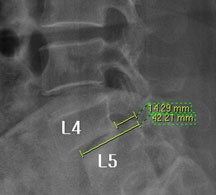

모커리한방병원 위 뼈가 50%정도 밀려나간 모습 이미지

척추전방전위증은 척추 주변, 특히 척추 후방에 있는 후관절 주변의 근육과 인대 그리고 후관절 자체가 퇴행되어 척추 뼈를 제대로 붙잡아 주지 못해 위아래 척추 뼈가 앞뒤로 밀려 나가면서 발생하는 척추질환을 말합니다.